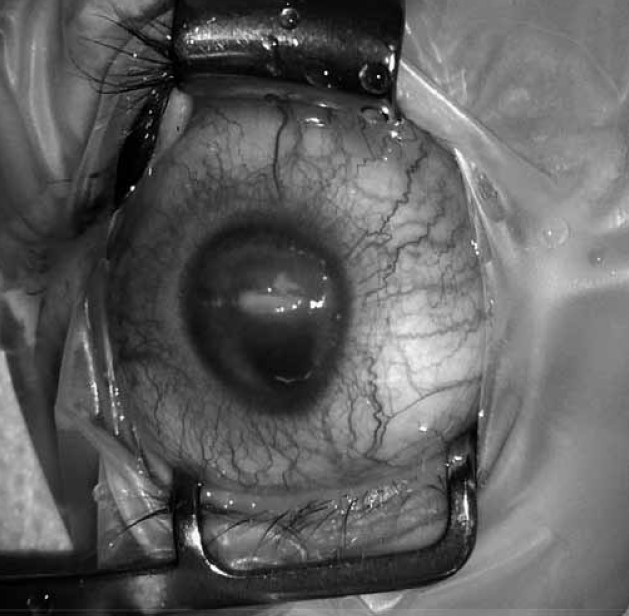

По результатам обследования выставлен диагноз «киста зрительного нерва», вероятнее всего, также колобоматозной природы. Учитывая наличие лагофтальма, приведшего к развитию ксероза роговицы с угрозой ее перфорации, было принято решение об оперативном лечении. В целях получения быстрого результата, с одной стороны, при минимальной инвазивности вмешательства — с другой, запланирована пункция и дренирование кисты зрительного нерва.

Произведена трансконъюнктивальная орбитотомия через верхний конъюнктивальный свод, мобилизован участок стенки кисты (рис. 7), после пункции получено 7 мл жидкости светло-желтого цвета. Выполнено цитологическое исследование полученного содержимого кисты — соломенно-желтая, прозрачная, белок 2,74 г/л, глюкоза 1,6 ммоль/л, цитоз 34/3. Цитоз представлен нейтрофилами, лимфоцитами, единичными макрофагами и неизмененными эритроцитами. От спинномозговой жидкости содержимое кисты отличалось значительно более высоким содержанием белка (в норме в ликворе до 0,33 г/л), низким уровнем глюкозы (в ликворе 2,8–3,9 ммоль/л) и высоким содержанием клеток (цитоз ликвора в норме 6–9/3).

Рис. 7. Ревизована колобоматозная киста правой глазницы, которая затем была пунктирована